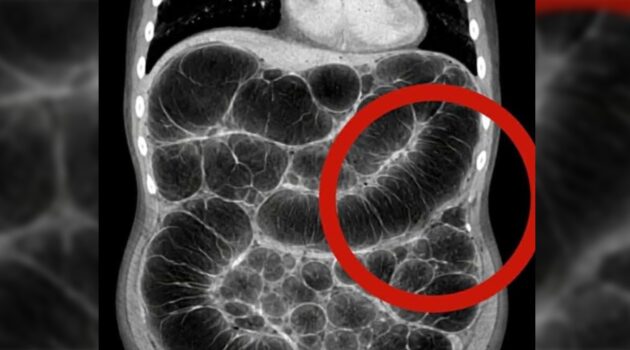

1. Overview of Frequent Gas and Bloating Experiencing constant intestinal gas can be uncomfortable and frustrating. While many people blame their diet…